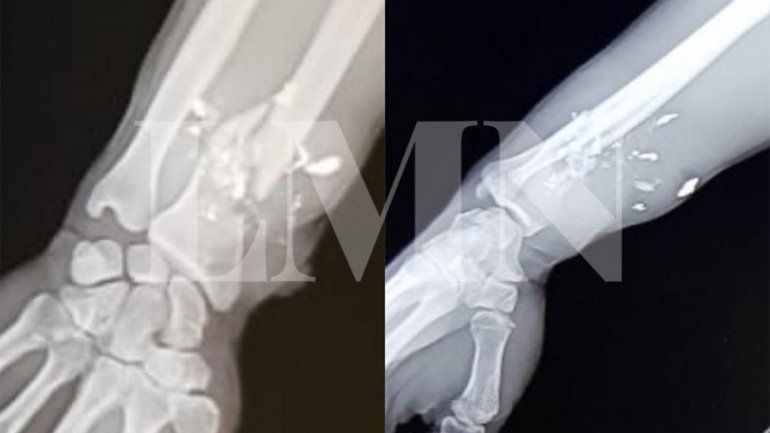

Marcos Condinanzo, el efectivo de la Policía Federal que resultó herido en su muñeca derecha, se encuentra actualmente con licencia médica sin poder recuperar la movilidad de los dedos índice, pulgar y medio de su mano hábil.

“Me sacaron un hueso de la cadera para ponérmelo en el brazo. Los médicos me dijeron que no voy a poder utilizar el arma”, expresó el policía, quien debió ser operado en tres oportunidades tras sufrir una fractura expuesta del radio. Así, sostuvo que no podrá continuar con la proyección de su carrera dentro de la fuerza.